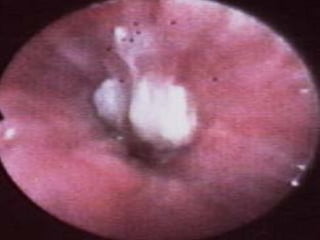

Bouchon muco-inflammatoire obstruant les VAD

chez un patient décédé d’ABPA

Fibroscopie bronchique

Inflammation bronchique diffuse.

Hypersécrétion blanchâtre ou brunâtre réalisant de

véritables bouchons muqueux difficiles à évacuer.

Liquide de fibro-aspiration : isolement d’A.fumigatus

(non pathognomonique).

LBA : alvéolite eosinophilique.

Biopsie bronchique : absence d’aspergillus dans la

paroi bronchique.